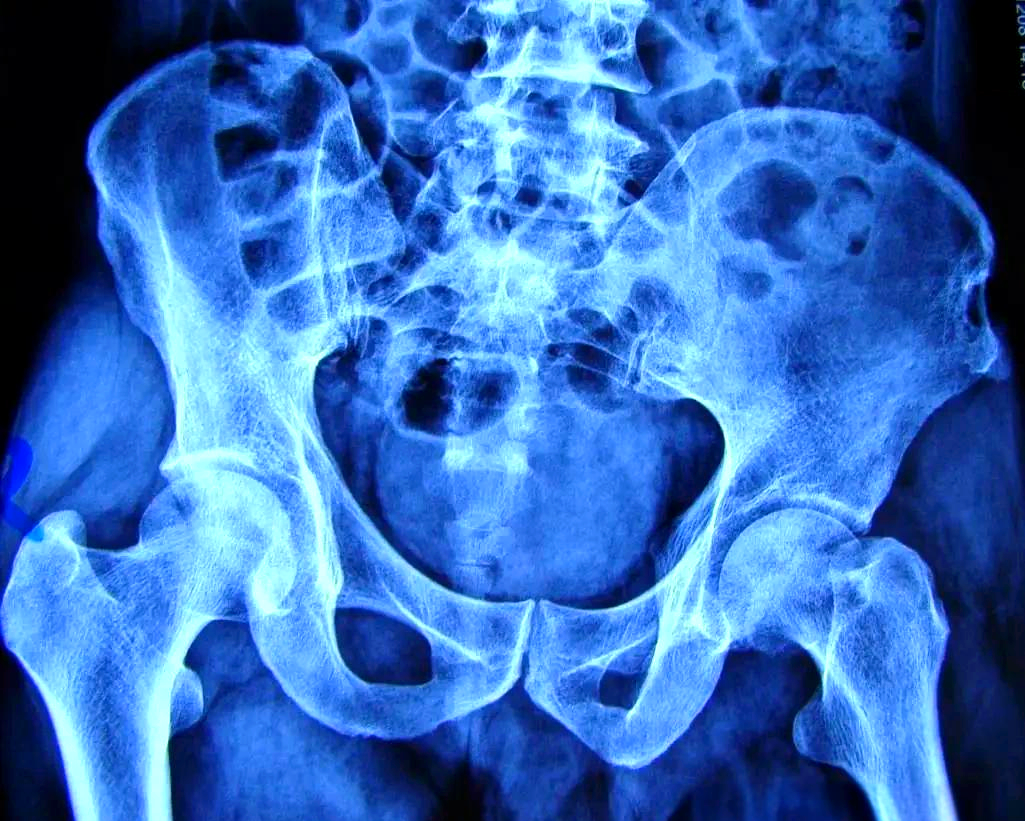

子宫下垂的症状主要有以下几方面腹部坠胀感与疼痛患者常出现腹部坠胀感,久站行走劳累或下蹲后更明显这是因为下垂的子宫牵拉压迫周围组织,导致局部血液循环不畅部分患者伴有腰骶部疼痛,可放射至下肢,休息后可能缓解年龄较大体质较...